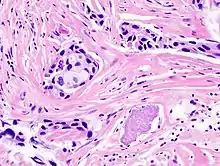

Classification of cancers has been dominated by the fields of histology and histopathology which aim to leverage morphological markers for accurate identification of a tumor type. Histological methods rely on chemical staining of tissues with pigments such as haematoxylin and eosin and microscopy-based visualization by a pathologist. The identification of tumor subtypes is based on established classification schemes such as the International Classification of Diseases published by the World Health Organization which provides codes to classify diseases and a wide variety of signs, symptoms, abnormal findings, complaints, social circumstances, and external causes of injury or diseases. For some types of cancer, these methods are unable to distinguish between subclasses; for example, defining subgroups of diffuse large B-cell lymphoma (DLBCL) have largely failed due to discrepancies between inter- and intra-observer reproducibility.[1] Furthermore, the clinical outcomes of tumors classified as DLBCLs is highly variable[1] suggesting that there are multiple subtypes of DLBCL that cannot be distinguished based on these histological markers. Breast tumor classification too has largely failed based on these predictors.[2] Development of effective therapies depends on accurate diagnosis; additionally, poor diagnosis can lead to patient suffering due to needless side-effects from non-targeted treatments and to increased health care expenditure. Most telling perhaps is that 70-80% of breast cancer patients receiving chemotherapy based on traditional predictors would have survived without it.[3][4]